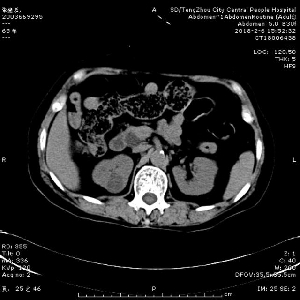

近日,消化內(nèi)二科為一名急性梗阻化膿性膽管炎合并感染性休克患者進(jìn)行急診ERCP(十二指腸鏡逆行性胰膽管造影術(shù))手術(shù)治療,成功解除膽道梗阻,挽救了患者寶貴的生命,并讓患者在除夕夜和家人團(tuán)聚,開心過上了春節(jié)。 2